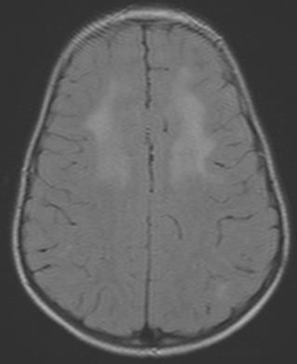

Diagnosis: Diagnosis is clinical, however, where available, neuro-imaging of the brain may show basal ganglia calcification, cerebral atrophy, and white matter changes.